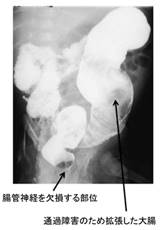

3)ヒルシュスプルング病(巨大結腸症)

結腸(大腸)の神経の異常や何らかの炎症性疾患などが原因となって結腸の蠕動運動が正常に行われず、

腸が大きく膨らむ病気のことです。

腸管神経系の先天性欠損があり、 機能的腸閉塞(先天性の腸閉塞疾患)です。